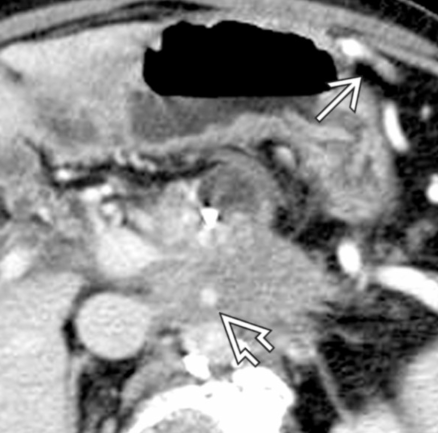

- Infiltration artérielle: <180° vs >180° et cranio-caudalement >2cm vs <2cm

- Infiltration veineuse: Contact, engainement, sténose, occlusion

- Infiltration de la lame rétroporte (entre l’AMS et l’uncus)

- Varices gastro-epiploiques si sténose VMS ou Veine splénique

Critères de résequabilité